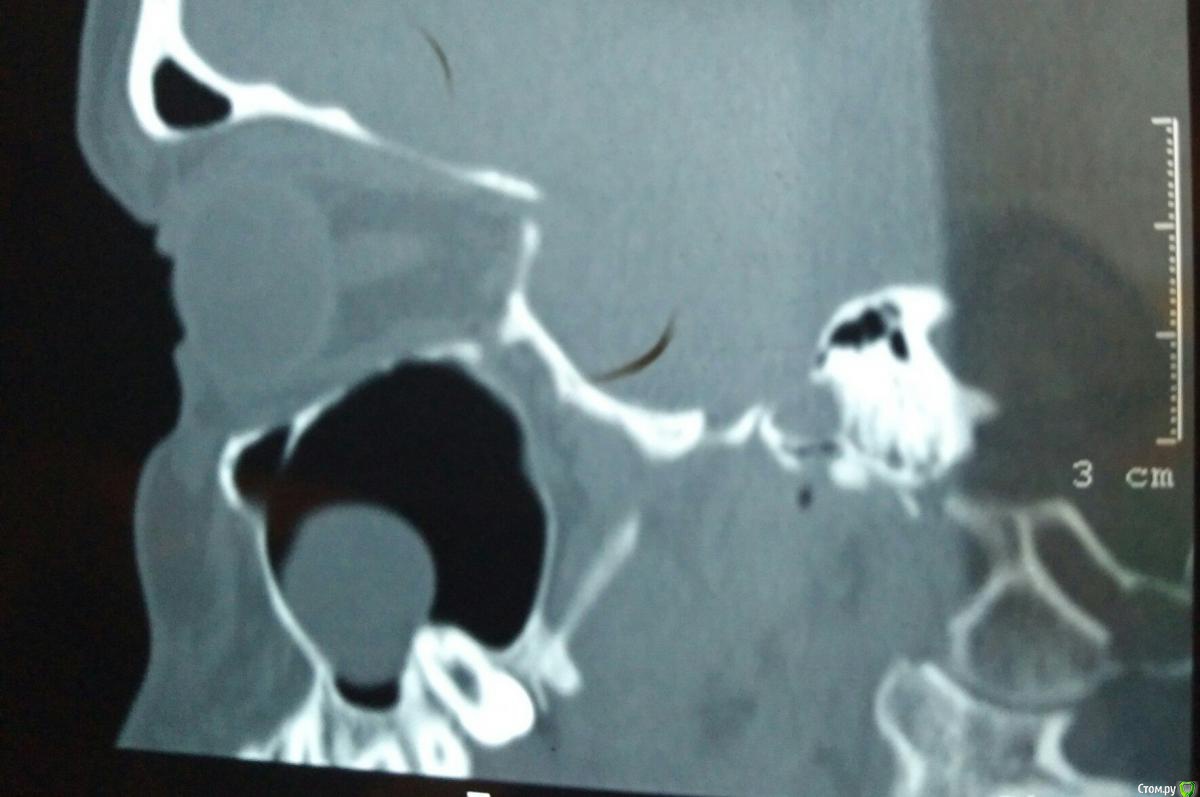

tineola Опубликовано 11 марта, 2017 Поделиться Опубликовано 11 марта, 2017 (изменено) Уважаемые врачи, здравствуйте! Мне 31 год, пол женский. Хронология:1. Ноябрь 2015 г. - септопластика и удаление кисты в левой гайморовой пазухе.2. Июль 2016 г. - со стороны этой же пазухи пролечены каналы 6-ки, через неск. дней удалена соседняя 7-ка (опустился почти до десны, беспокоил, ортодонты сошлись во мнении, что надо удалять).Через неделю появились незначительные боли в 6-ке, возникающие безотносительно нагрузки на зуб и еду. На прицельном рентгене корни 6-ки и лунка от 7го зуба были в порядке. Стоматолог уверял, что боль вызвана заживлением лунки от удаленного зуба и много других версий. Поэтому я ждала улучшений и терпела все это время.3. В последние недели боль усилилась: возникает при поворотах, наклонах головы, появились головные боли, головокружения, заложенность в носу. Сделала КТ конкретной области беспокоящего зуба, на которой видно новообразование в левой гайморовой пазухе, как бы лежащее на корнях беспокоящей 6-ки. Стоматологи предполагают, что киста от зуба мудрости (т.е. одонтогенная), возможно, рецидив первой. К посту прикрепила:1. ОПТГ (сделана до лечения 6-ки и удаления 7-ки, но после септопластики и удаления кисты).2. Фото из свежей КТ зубов с разных ракурсов, где хорошо видно новую кисту; ссылка на Яндекс-диск с архивом этого КТ (около 350 Мб) - https://yadi.sk/d/9omJkw6x3Efc6u3. Фото одной из проекций из старой КТ ОНП до септопластики, так выглядела старая киста. 4. К сожалению, результатов гистологии первой кисты у меня нет. В центре, где меня оперировали заключение не отдали, только сказали на словах, что все в результатах нормально. Попробую на руки получить...Очень интересует ваше мнение об увиденном на снимках.Правильно я понимаю: киста от зуба мудрости? удалять надо в ЧЛХ зуб с кистой вместе? Не пострадали ли от долгого ожидания решения проблемы корни 6-го зуба? Заранее большое спасибо за помощь! Изменено 11 марта, 2017 пользователем tineola Ссылка на комментарий

tineola Опубликовано 15 марта, 2017 Автор Поделиться Опубликовано 15 марта, 2017 (изменено) Сделала несколько скриншотов, прикрепляю к сообщению. Надеюсь, это то, что нужно.Может у кого-то из врачей будет время и возможность посмотреть КТ (ссылка в первом сообщении поста). Получила результаты гистологии первой кисты пазухи, которая год назад была удалена:Микроописание: Присланный материал представлен фрагментом полипозно-отечной слизистой оболочки, с концевым отделами слизисто-серозных желез. Эпителий слущен, гиалиоз базальных мембран, строма резко отечна, с диффузной лимфоцитарно-лейкоцитарной инфильтрацией. Патзаключение: хронический воспалительный процесс. Изменено 15 марта, 2017 пользователем tineola Ссылка на комментарий